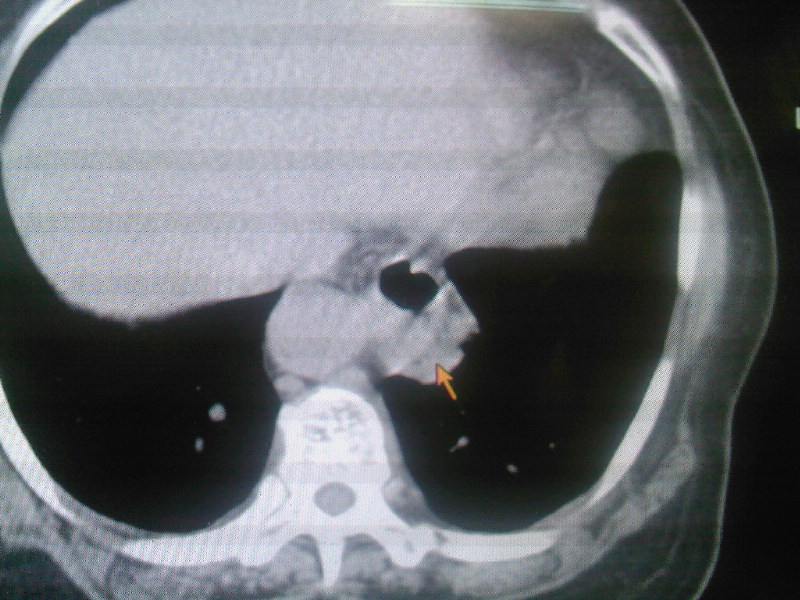

食管下段近贲门处可见前方一限局性空腔影。想临食管避受压,且与食管分界不清,跨与食管裂孔处,顶部位于中后纵膈,请指教

1:食管裂孔疝?2:食管癌溃疡纵隔瘘?服造影剂检查观察一下。